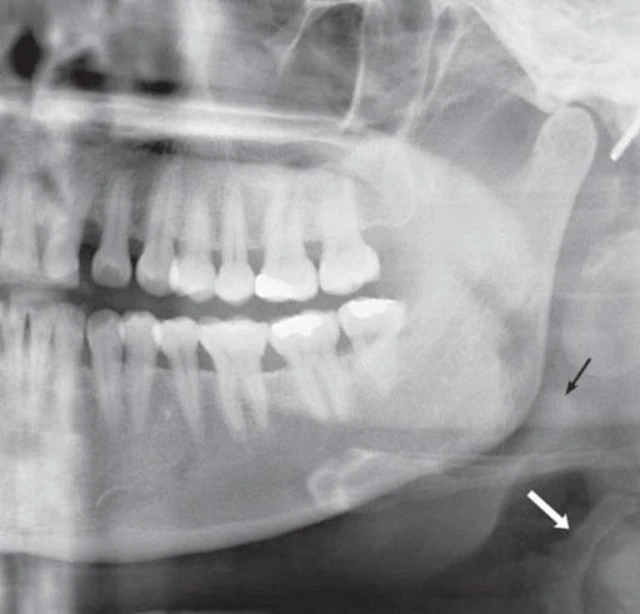

Hình 21. Những cấu trúc thường thấy ở vùng cổ trên phim x-quang toàn cảnh. Mũi tên trắng cho thấy mặt trên của sụn tuyến giáp, có thể bị nhầm với vôi hoá mạch máu. Mũi tên đen chỉ nắp thanh quản. Cũng nên lưu ý rằng hình của trang sức mang trên tai nằm phía sau đầu lồi cầu xương hàm dưới.

Hình 22. Rãnh chân bướm hàm, một khoảng trống giữa mặt sau xương hàm trên và bờ trước của cánh chân bướm. A, Hình giọt nước ngược của rãnh trên phim toàn cảnh (mũi tên). B, Rãnh trên sọ khô (mũi tên). C, Phần hình ảnh xấp xỉ lớp ảnh của phim x-quang toàn cảnh đi qua rãnh chân bướm hàm trên lát cắt trục của phim CT (thanh trắng).